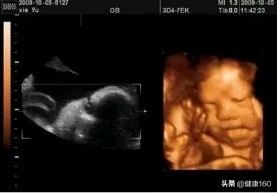

三维彩超、四维彩超的图像则是后期生成的,并不是说观察到的图像就是三维、四维的,而是仍然用普通彩超观察,然后通过仪器中的转换软件将观察到的平面图像转成三维、四维的立体图像。

说得更直白一点,如果将你的家用电脑中装上类似软件,你就可以把普通B超的图像自己在家里转换成立体的了。在诊断的意义上,三维、四维没有任何对诊断更有利的地方,只不过是不懂得B超图像的人也能看出模样而已。它的意义也就在于,您能看见宝宝在肚子里的立体模样了。